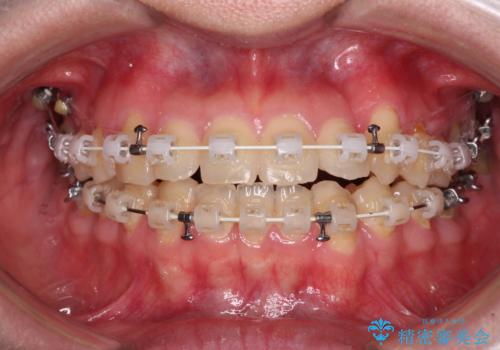

- 矯正装置

- 審美装置

- 八重歯を気にして来院された患者様です。

診査を行ったところ、下顎前歯が1本欠損しており、下顎歯列が上顎よりも小さくなっていることで、上顎にデコボコが生じていました。

口元を見ると抜歯をして突出感を改善するような状態ではなかったため、上顎歯列のデコボコを整えて、歯列全体を後方に移動させることでバランスを取ることとしました。

マウスピース矯正は自己管理が煩わしいとのことで、ワイヤー装置にて矯正治療を行うこととしました。